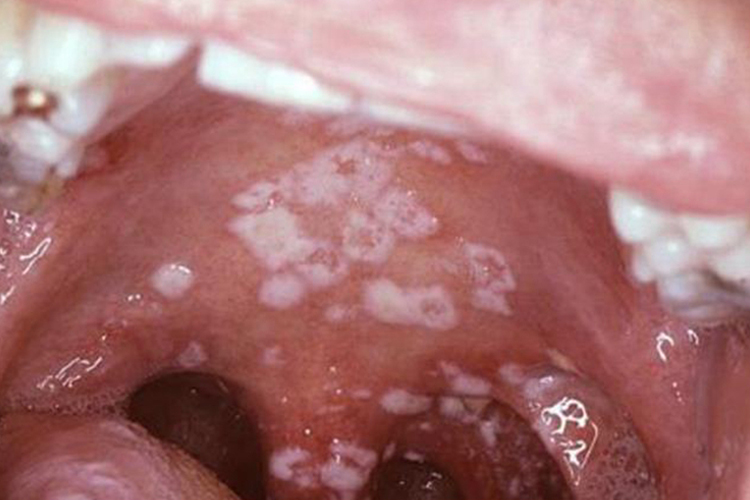

鹅口疮早期症状可表现为黏膜充血,散在的白色小斑点,如帽针大小,一般无全身症状,该疾病是由于白色念珠菌感染所致。

鹅口疮多好发部位为颊、舌、软腭及唇,早期损害区黏膜充血,可出现散在的色白如雪的柔软小斑点,如帽针头大小。随疾病进展,不久即相互融合为白色丝绒状斑片,可继续扩大蔓延,严重者波及扁桃体、咽部。斑片擦掉可暴露红的黏膜糜烂面,并有轻度出血。